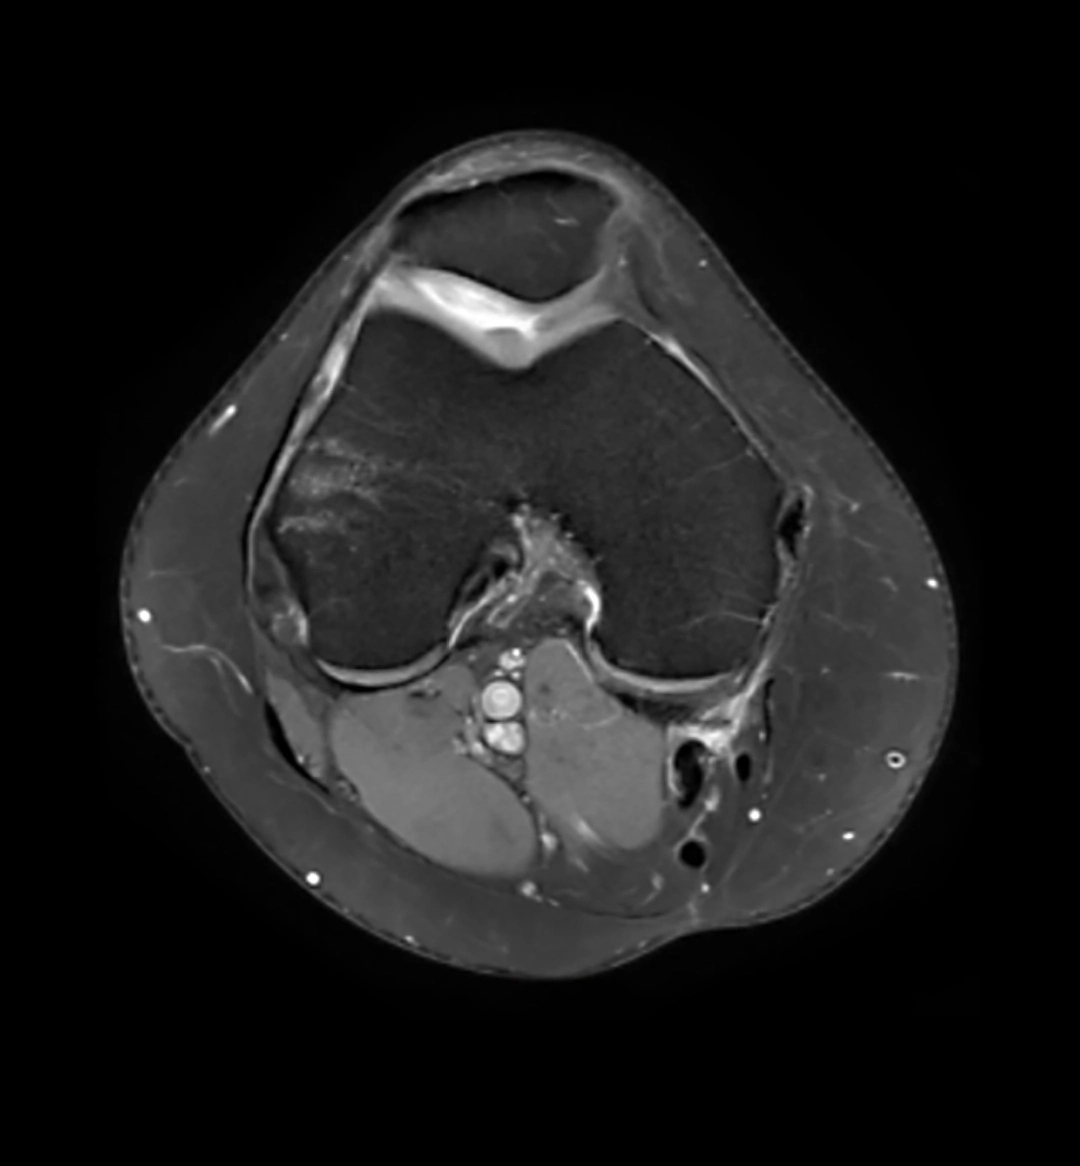

La RM 3T permite obtener imágenes de altísima resolución, con un nivel de detalle superior al de los equipos convencionales. Gracias a ello, se facilita la correcta valoración de estructuras complejas como:

Cartílago

Meniscos

Ligamentos

Tejidos blandos

Esta capacidad de detalle resulta fundamental para detectar lesiones con mayor exactitud y reducir el margen de error diagnóstico.

Estudio de rodilla mediante RM 3 Teslas de VOT, con alta definición anatómica y excelente contraste tisular para una valoración precisa de estructuras osteoarticulares y partes blandas.